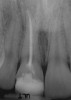

Figure 6a  Upper right central incisor, history of trauma, existing RCT and restoration unsatisfactory.

Figure 6a

Figure 6b  Upper right central incisor, history of trauma, existing RCT and restoration unsatisfactory.

Figure 6b

Figure 6c  Upper right central incisor, history of trauma, existing RCT and restoration unsatisfactory.

Figure 6c